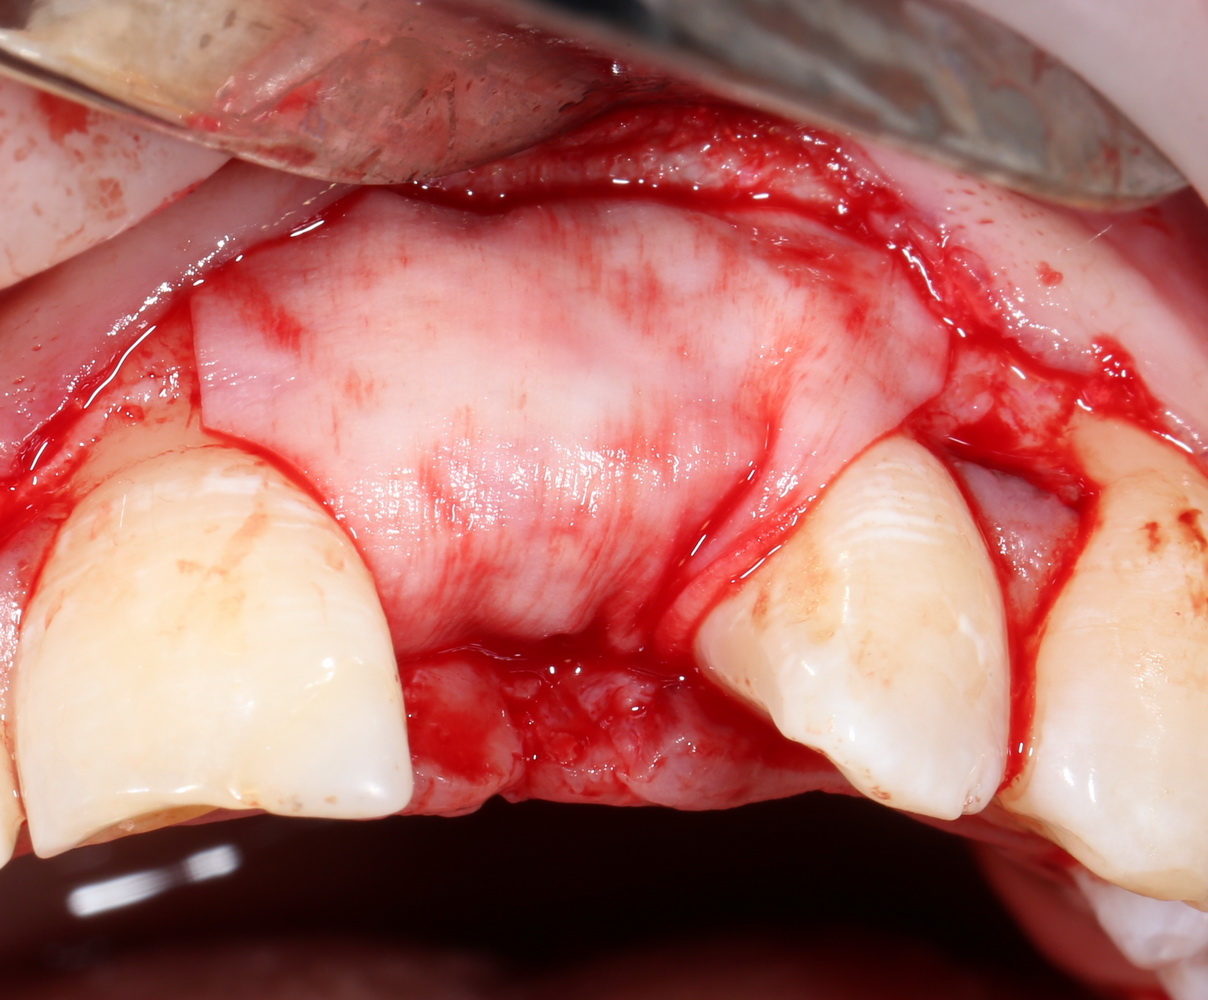

Другой вариант. Имплантируем, но существующего объема костной ткани недостаточно для получения адекватного эстетического и функционального результата:

Поэтому мы используем мембрану Geistlich BioGide и всё ту же аутокостную стружку:

Вот чем мне нравится мембрана BioGide — так это своими свойствами. Предсказуема до мелочей.

Во влажном состоянии она эластична и податлива, поэтому нет необходимости использовать пины или винты:

ну и, швы: